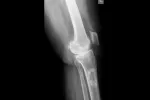

El tipo de cáncer de huesos más común es el osteosarcoma, que tiene su origen en los osteoblastos, que son las células óseas que generan el hueso nuevo. El osteosarcoma es un tumor óseo maligno que destruye el tejido óseo normal.

• Localización: fémur distal y tibia proximal, que son los huesos que forman la articulación de la rodilla. También es frecuente que aparezca en el fémur proximal (cerca de la cadera) y el húmero proximal (cerca del hombro).

• Clínica: los síntomas más frecuentes son el dolor, que se acentúa con el movimiento, y el aumento de tamaño de una parte del hueso, que puede entorpecer la función de la articulación más cercana (casi siempre la rodilla). Además, el hueso, al estar debilitado por la acción del tumor, es más susceptible de fracturarse.